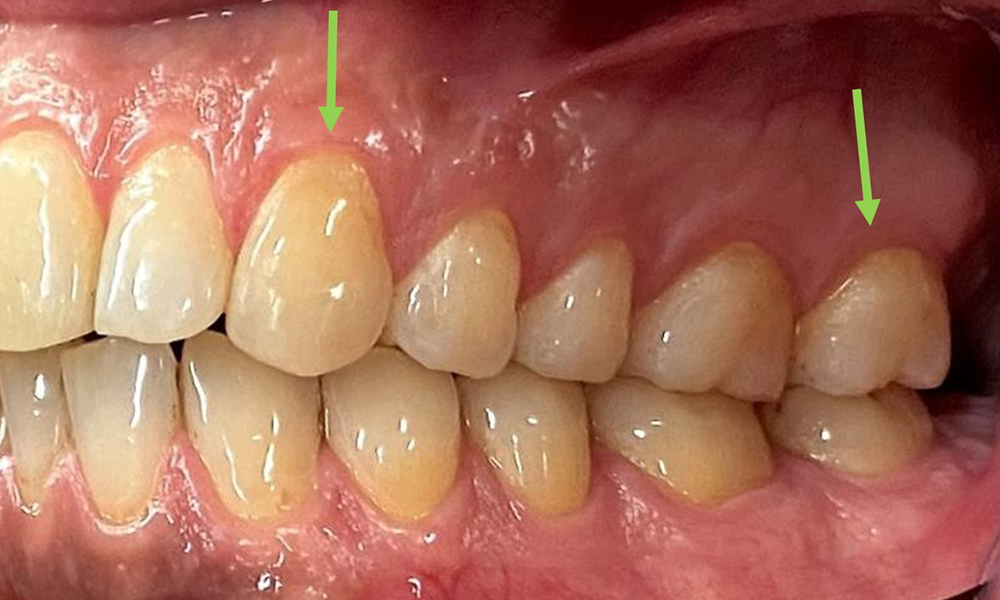

Nahaufnahme der Zähne

Abb. 5: Nahaufnahme der Zähne 45-47. Grüne Pfeile zeigen Attritionen und Erosionen im Bereich der bukkalen Höcker mit partiellem Schmelzverlust, © Dr. R. Krapf

Dental zeigt sich ein vollbezahntes Gebiss mit 28 Zähnen. Auffällig sind Erosionen und Attritionen

(Abb. 4, Abb. 5). Der Patient trägt seit vielen Jahren nachts eine Schiene mit adjustiertem Aufbiss aufgrund Bruxismus. Die Erosionen sind auf den langjährigen Konsum isotonischer Getränke zurückzuführen. Parodontaler Knochenverlust und aktive kariöse Läsionen sind nicht vorhanden.